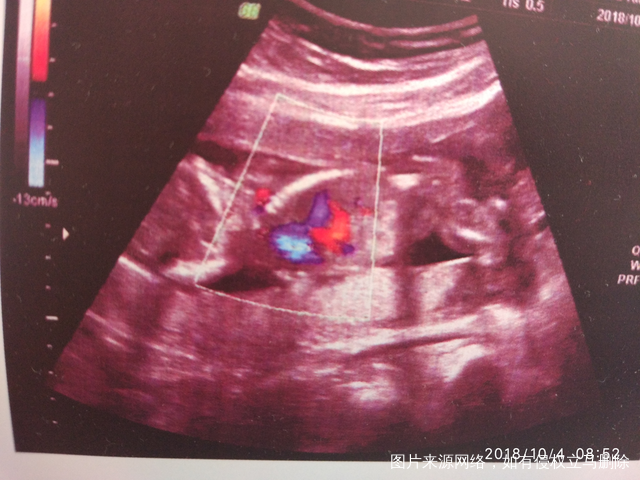

昨天做的唐筛,等待结果……

B超一切正常,就是好奇男女宝宝[大笑][大笑][大笑]

有会看的吗,猜猜看[调皮][调皮][调皮]